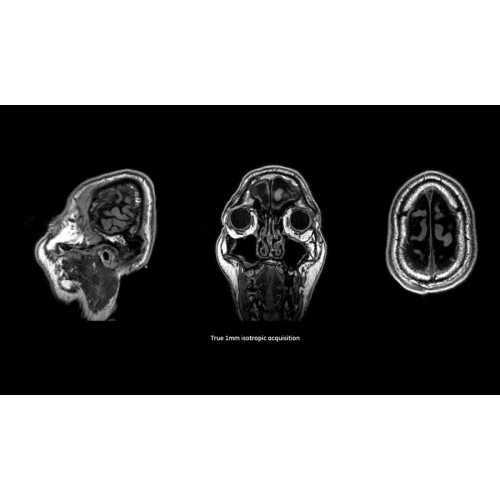

Система SIGNA Pioneer воплощает поразительные достижения в области визуализации. Передовая технология Total Digital Imaging (TDI) позволяет добиться большей четкости изображений и на четверть повысить соотношение сигнал/шум.

TDI построена на трех базовых компонентах:

• Технология Direct Digital Interface (DDI) использует независимый аналого-цифровой преобразователь для оцифровки сигнала от каждого из 97 радиочастотных каналов, что обеспечивает значительное увеличение качества за счет уменьшения фонового шума.

• Технология Digital Micro Switching (DMS) — это следующее поколение технологий радиочастотных катушек, основанное на замене аналоговых схем блокировки сверхбыстрыми микропереключателями (MEMS), что делает возможным быстрое переключение катушек для дальнейшего расширения возможностей визуализации с нулевым TE.

• Технология Digital Surround Technology (DST) — это новая технология объемной оцифровки данных, объединяющая сигналы от каждого элемента катушки. Прекрасное соотношение сигнал/шум и чувствительность поверхностных катушек в сочетании с превосходной однородностью и высокой проникающей способностью встроенной радиочастотной катушки — все это позволяет создавать качественные изображения не только позвоночника, но и всего тела.

Помимо технологии 97 РЧ-каналов, SIGNA Pioneer использует магнит 3.0Т высокой однородности, предназначенный для повышения качества визуализации во всех областях, а также закладывающий прочный фундамент для долгосрочных инвестиций и роста клинических возможностей.